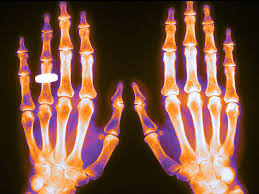

Denosumab 60 mg : mayor riesgo de fracturas vertebrales múltiples después de interrumpir o retrasar el tratamiento en curso

Evalúe los factores individuales de un paciente en cuanto a beneficios y riesgos antes de iniciar el tratamiento con denosumab 60 mg, especialmente en aquellos con fractura vertebral previa. Los pacientes no deben interrumpir el tratamiento con denosumab sin la revisión de un especialista. Drug Safety Update, 26 de Agosto de 2020